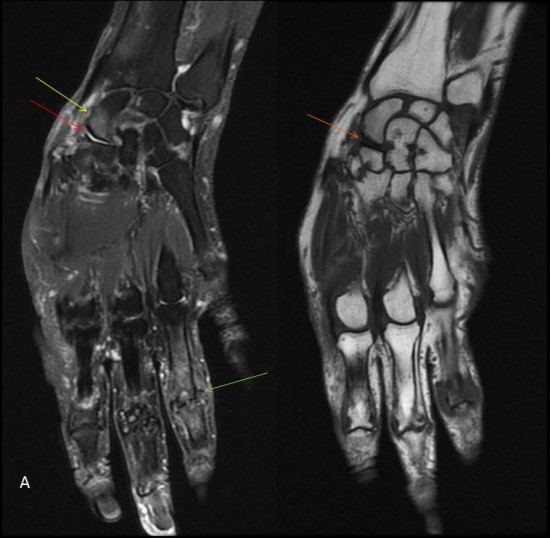

Le poignet (IRM) : atlas d’anatomie en imagerie médicale